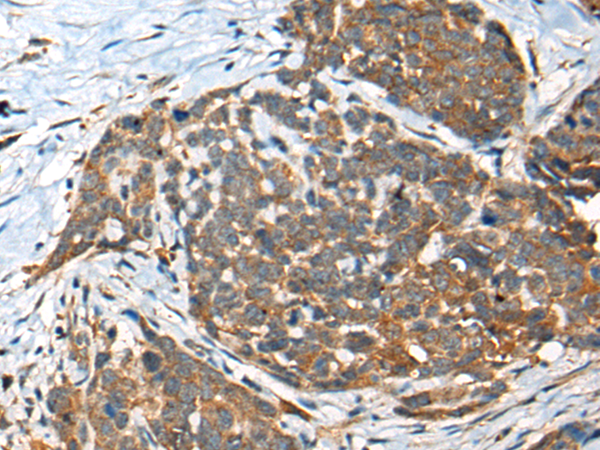

分类: 科研抗体货号: P12859别名: YB1; BP-8; CSDB; DBPB; YB-1; CBF-A; CSDA2; EFI-A; NSEP1; NSEP-1; MDR-NF1应用: IHC反应种属: Human, Mouse, Rat